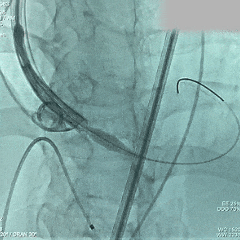

展开后造影,瓣膜位置偏深

回收后再次释放

第二次展开造影,瓣膜位置尚可,基本无漏

多角度评估,瓣膜深度可